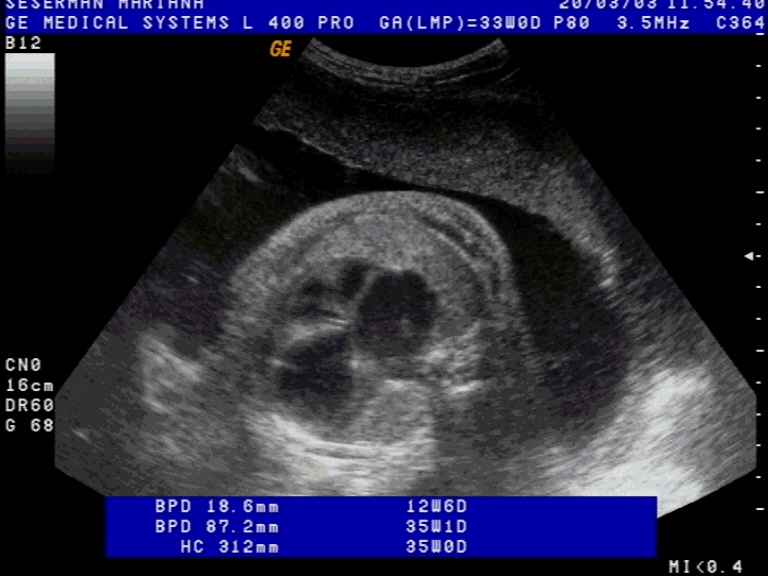

Anomaly: Stenoza mitrala. Stenoza aortica. Fibroelastoza endocardica date: 2004-05-28

Diagnosis at 32 GA by TAS Previous Normal Scan Previous Normal Scan at 17 GA

Thorax and heart

Hipoplazia inimii stangi

Macroscopic: Cord-stenoza mitrala, stenoza aortica, cardiomegalie cu fibroelastoza. anomalie minora lobara pulmonara bilaterala. Ascita 100 ml

Microscopic: Ingrosarea endocardului prin fibre elastice si tesut conjunctiv.

Naste un fat mort intrapartum de sex feminin 2400 gr.

GA at delivery / abortum: 32